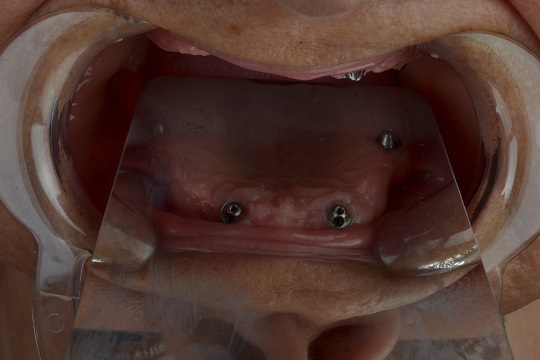

Nakon preoperativnih priprema, ako je potrebno, izvade se preostali malobrojni zubi (ako ih ima i loši su), i postavljaju se na tačno utvrdjena mesta posebni implanti, vodeći računa o okolnim anatomskim strukturama. Dva implanta se postavljaju u frontalnu regiju gde je volumen kosti veći, i gde se očekuje najmanja atrofija kosti, a druga dva implanta se postavljaju u bočnoj regiji pod uglom od 45 stepeni, kako bi budući zubi bili stabilniji, vodeći računa o bitnim anatomskim parametrima, tj maksilarnom sinusu u gornjoj i mandibularnom kanalu u donjoj vilici.

Nakon par sati koliko intervencija traje, uzimaju se otisci i pacijent nakon par proba dobija kroz dan/dva privremene zube koji izgledaju kao prirodni.